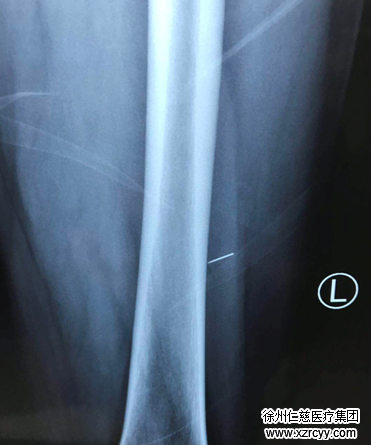

17日一大早,谢先生和妻子来到必威官方首页官网betway,接诊的手外科二病区唐洪伟医生看了片子后,发现这根针从患者大腿后侧刺入,位置非常深,基本已刺到骨头。如果不取出,随着患者走路运动,绣花针会随之上下游走,一旦刺伤重要的血管神经,会造成大出血、深部组织感染、肌肉坏死等,后果将会非常严重。

局部麻醉后,在1.5cm微创小切口内,唐医生仔细探查发现,由于病人的行走,绣花针随着肌肉的移动开始游走,已经和皮肤针眼不在一个平面。唐医生凭借经验以及肌肉运动的轨迹,用止血钳一点一点去寻找这根断针,“过程就像大海捞针一样,你无法准确判断那根针游走到了什么位置。”唐医生说,就在一点点的摸索中,突然一下感觉碰到了断针,于是他迅速用一把止血钳夹住断针并固定,防止其脱落,然后又拿来另一把钳子将其完整取出。

最终,这根长约1.5cm的断针被医生小心翼翼地从谢先生体内取出。谢先生感激不已地说“这下好了,不用住院,终于取出来了,还是你们医术高超。”伤口缝合好后,谢先生休息了一会儿便回家了。